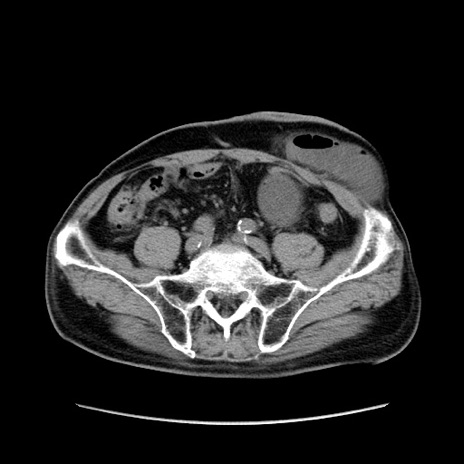

症例24(横断像)

【症例】80歳代男性

【主訴】左側腹部痛、嘔吐

【現病歴】本日早朝より左腹部に痛みあり。昼頃嘔吐認めたため、救急要請。

【既往歴】直腸癌(Mile手術)、胆摘

【身体所見】意識清明、BT 35.9℃、BP 221/93mmHg、SpO2 97%(RA) 、腹部:左ストーマ周囲に限局性の腹部膨隆あり。 膨隆部自発痛・圧痛あり・軟。

【データ】WBC 7700、CRP 0.09